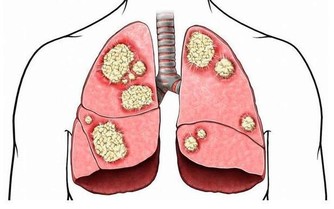

作為人體的消化系統,我們注意對胃部的保護,減少吃垃圾食品和比較硬的食物,

多喝小米粥,多吃蔬菜,能夠幫助腸道消化,保持胃酸處於平衡狀態。

胃酸能夠引起口臭的情況發生,我們除了要保養腸胃,還要常做這4件事,能夠較好的預防因胃病而引起的口臭。對於胃部養生,你還知道哪些呢?